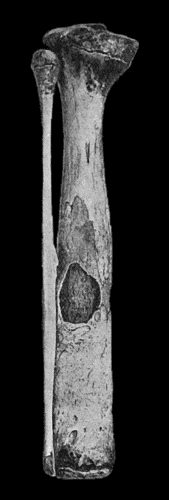

| 67. | Extensive Varix of Internal Saphena System on Left Leg | 291 |

| 153. | Epitheliomatus Ulcer of Leg invading Tibia | 499 |